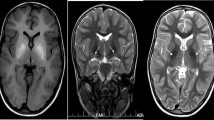

Homeostasis of Mn levels in the body is tightly regulated through intestinal absorption and hepatobiliary secretion of the metal into the gastrointestinal tract [7]. Due to its ubiquity, dietary Mn deficiency has not been reported. Toxicity through overexposure on the other hand has been well documented in occupational exposure in miners, welders, battery manufacturers and ferroalloy workers [3, 8]. Excess Mn mainly accumulates in the basal ganglia, particularly the globus pallidus, causing a distinct extrapyramidal syndrome known as manganism. Symptoms include initial cognitive and psychiatric disturbances followed by a movement disorder resembling Parkinson’s disease with limb rigidity, dystonia and a characteristic high-stepping gait [3, 9]. Deposition of the paramagnetic metal in the brain causes distinct MRI brain appearances with pronounced hyperintensity of the globus pallidus on T1-weighted and hypointensity on T2-weighted images [10]. Other causes for acquired manganism include high concentrations of Mn in drinking water, parenteral nutrition and Mn contaminated ephedrone preparations [3, 9]. Impaired hepatobiliary excretion of Mn in end-stage liver disease similarly leads to Mn overload, a condition described as acquired hepatocerebral degeneration [11].

The first hereditary disorder of Mn metabolism associated with Mn neurotoxicity was reported in 2012 [21••, 22••]. Mutations in SLC30A10 lead to a syndrome of hypermanganesaemia with dystonia, polycythaemia and chronic liver disease, now referred to as hypermanganesaemia with dystonia 1 (HMNDYT1) (OMIM #613280). Mainstay of treatment is chelation therapy with intravenous disodium calcium edetate (EDTA-CaNa2) in combination with iron supplementation [21••, 22••, 23,24,25]. In 2016, a similar hereditary Mn transporter defect, hypermanganesaemia with dystonia 2 (HMNDYT2) (OMIM #617013), was described that can be distinguished from SLC30A10 deficiency by absence of liver involvement and polycythaemia. Mutations in SLC39A14 lead to rapidly progressive dystonia with variable parkinsonism and other neurological signs with onset during infancy or early childhood. Chelation therapy with EDTA-CaNa2 has been attempted with some success [26••]. Both inherited Mn transporter defects share pathognomonic MRI brain appearances with hyperintensity on T1-weighted images of the globus pallidus and striatum, and the white matter of the cerebrum and cerebellum, midbrain, dorsal pons and medulla while the ventral pons is typically spared [21••, 22••, 26••].

Hypermanganesaemia with dystonia 1 (HMNDYT1) caused by bi-allelic mutations in SLC30A10 was the first inherited manganese transporter defect described [21••, 22••]. To date, more than 30 patients have been reported (Table 2). Systemic Mn accumulation leads to a distinct syndrome of hypermanganesaemia, polycythaemia, dystonia, chronic liver disease (ranging from asymptomatic steatosis to cirrhosis with liver insufficiency) and depletion of iron stores. Blood Mn levels are dramatically raised, on average reported as ten times that of normal. On brain MRI, deposition of Mn is evident in the basal ganglia, particularly the globus pallidus and striatum with pronounced hyperintensity of T1-weighted imaging and corresponding hypointensity on T2-weighted imaging [21••, 22••, 23, 39,40,41]. There is additional involvement of the white matter of the cerebrum and cerebellum, midbrain, dorsal pons and medulla with a pathognomonic sparing of the ventral pons (Fig. 1). Clinically, the majority of patients present with dystonia during early childhood. Lower limb dystonia causes a characteristic high-stepping gait, also described as “cock walk gait”. White matter involvement can cause spasticity and pyramidal tract signs. A late onset form presenting as adult parkinsonism unresponsive to L-DOPA treatment has also been reported in one family so far [21••]. Cognition is typically normal. Histologically, severe neuronal loss in the globus pallidus and a vacuolated myelinopathy have been observed in the only case with postmortem examination reported to date [47]. Accumulation of Mn in the liver is hepatotoxic and leads to liver disease. However, the liver is not always clinically involved, at least at disease presentation, and liver disease might range from mild forms (steatosis) to severe forms (cirrhosis). Some patients have died due to liver cirrhosis. Polycythaemia has been reported in all patients and can be present prior to clinical symptoms. It has been suggested that Mn induces erythropoietin gene expression. Indeed, erythropoietin levels have been raised in some affected individuals [20]. As Mn and Fe compete for binding at several transporters, it is not surprising that iron stores are depleted in individuals with SLC30A10 mutations who show an increased total iron-binding capacity and a low ferritin [21••, 22••].

Characteristic appearances of Mn deposition in HMNDYT1 and HMNDYT2 on brain MRI. a–c Individual with HMNDYT1. d–f. Individual with HMNDYT2. a, d T1-weighted sagittal imaging showing hyperintensity of the white matter of the corpus callosum (yellow arrow), cerebellum (pink arrow) and the dorsal pons (white arrow) with characteristic sparing of the ventral pons (*). b, e T1-weighted transverse imaging showing hyperintensity of the globus pallidus (blue arrow) and cerebral white matter (white arrow) bilaterally. c, f T2-weighted transverse imaging showing hypointensity of the globus pallidus (blue arrow) bilaterally corresponding to T1-hyperintensities [22••, 26••]. (Reprinted from: Tuschl, K. et al. Syndrome of Hepatic Cirrhosis, Dystonia, Polycythemia, and Hypermanganesemia Caused by Mutations in SLC30A10, a Manganese Transporter in Man, Am. J. Hum. Genet, 90 (2012) 457–466; with permission from Elsevier) [22••]. (Reproduced from Tuschl, K. et al. Mutations in SLC39A14 Disrupt Manganese Homeostasis and Cause Childhood-Onset Parkinsonism-Dystonia, Nat Commun, 7: 11601 doi: https://doi.org/10.1038/ncomms11601 (2016); Creative Commons user license http://creativecommons.org/licenses/by/4.0/) [26••]

MRI brain appearances are identical to those seen in HMNDYT1 (Fig. 1). Postmortem examination of one affected individual showed marked neuronal loss in the globus pallidus, patchy loss of myelin associated with coarse vacuoles in the cerebral and cerebellar white matter, and axonal loss [26••]. To date, a total of 16 patients have been reported (Table 2) [26••, 34, 43,44,45,46].